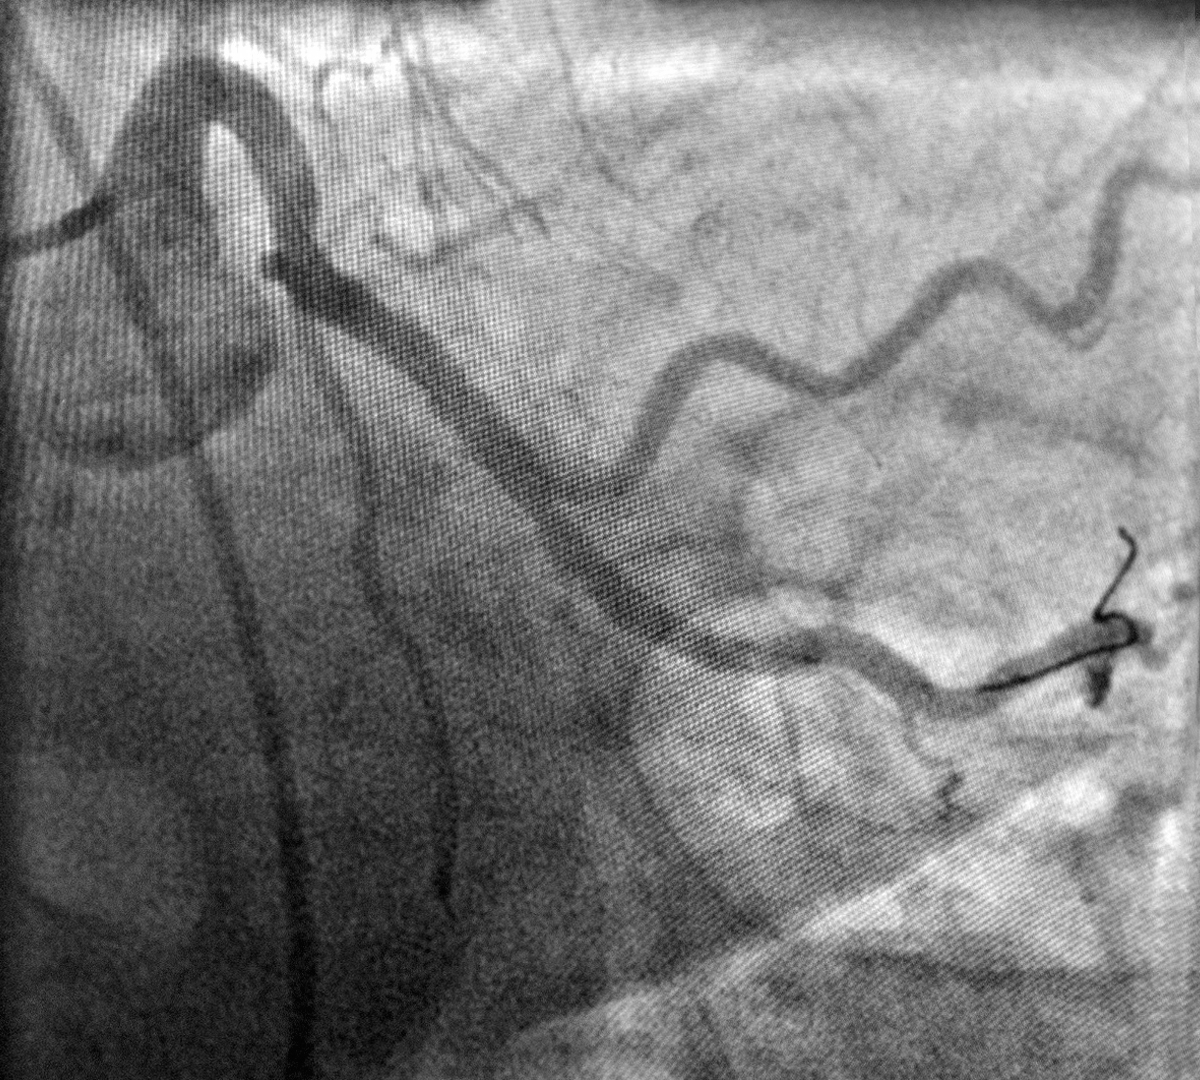

Ajunsă în sala de angiografie ARES Constanța, doctorul Nicolae Cârstea i-a efectuat angiografia coronariană, porcedură care evidențiează eventuale blocaje de la nivelul arterelor inimii.

În timpul procedurii, doctorul Cârstea a observat că pe una dintre arterele inimii ( ACX – artera circumflexă) există o îngustare, o stenoză de 80% responsabilă de durerea toracică resimțită de pacientă.

Tratamentul de elecție în astfel de cazuri este reprezentat de implantarea de stenturi, procedură denumită angioplastie coronariană. Practic, la nivelul vaselor îngustate, medicul cardiolog intervenționist implantează stenturi metalice pentru a reda circulația normală a sângelui și a salva mușchiul cardiac.

Astfel, în cazul prezentat mai sus, doctorul Nicolae Cârstea, medic cardiolog intervenționist la Ares Constanța, a efectuat angioplastia coronariană iar rezultatul este unul foarte bun.